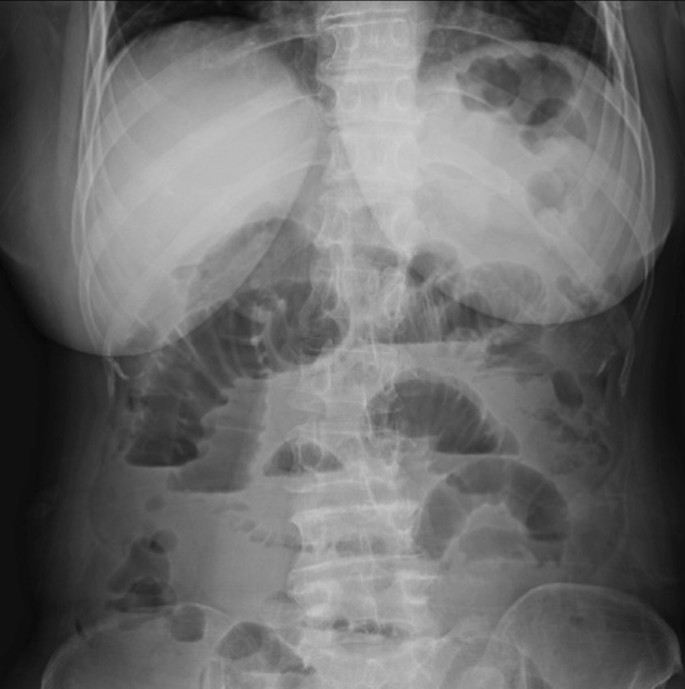

On the 6th postoperative day (POD), the patient developed abdominal bloating and nausea. Abdominal radiography revealed that the stomach and the intestine were markedly dilated with gas and air-fluid levels, indicating paralytic ileus (Fig. 3). Thus, the patient was initiated on fasting and fluid replacement therapy, following which she recovered completely within 4 days. On the 27th POD, the patient received the first cycle of combination chemotherapy consisting of paclitaxel (175 mg/m2; 3-h infusion) and carboplatin (at a dose corresponding to an area under the curve [AUC] of 5 mg/mL/min).